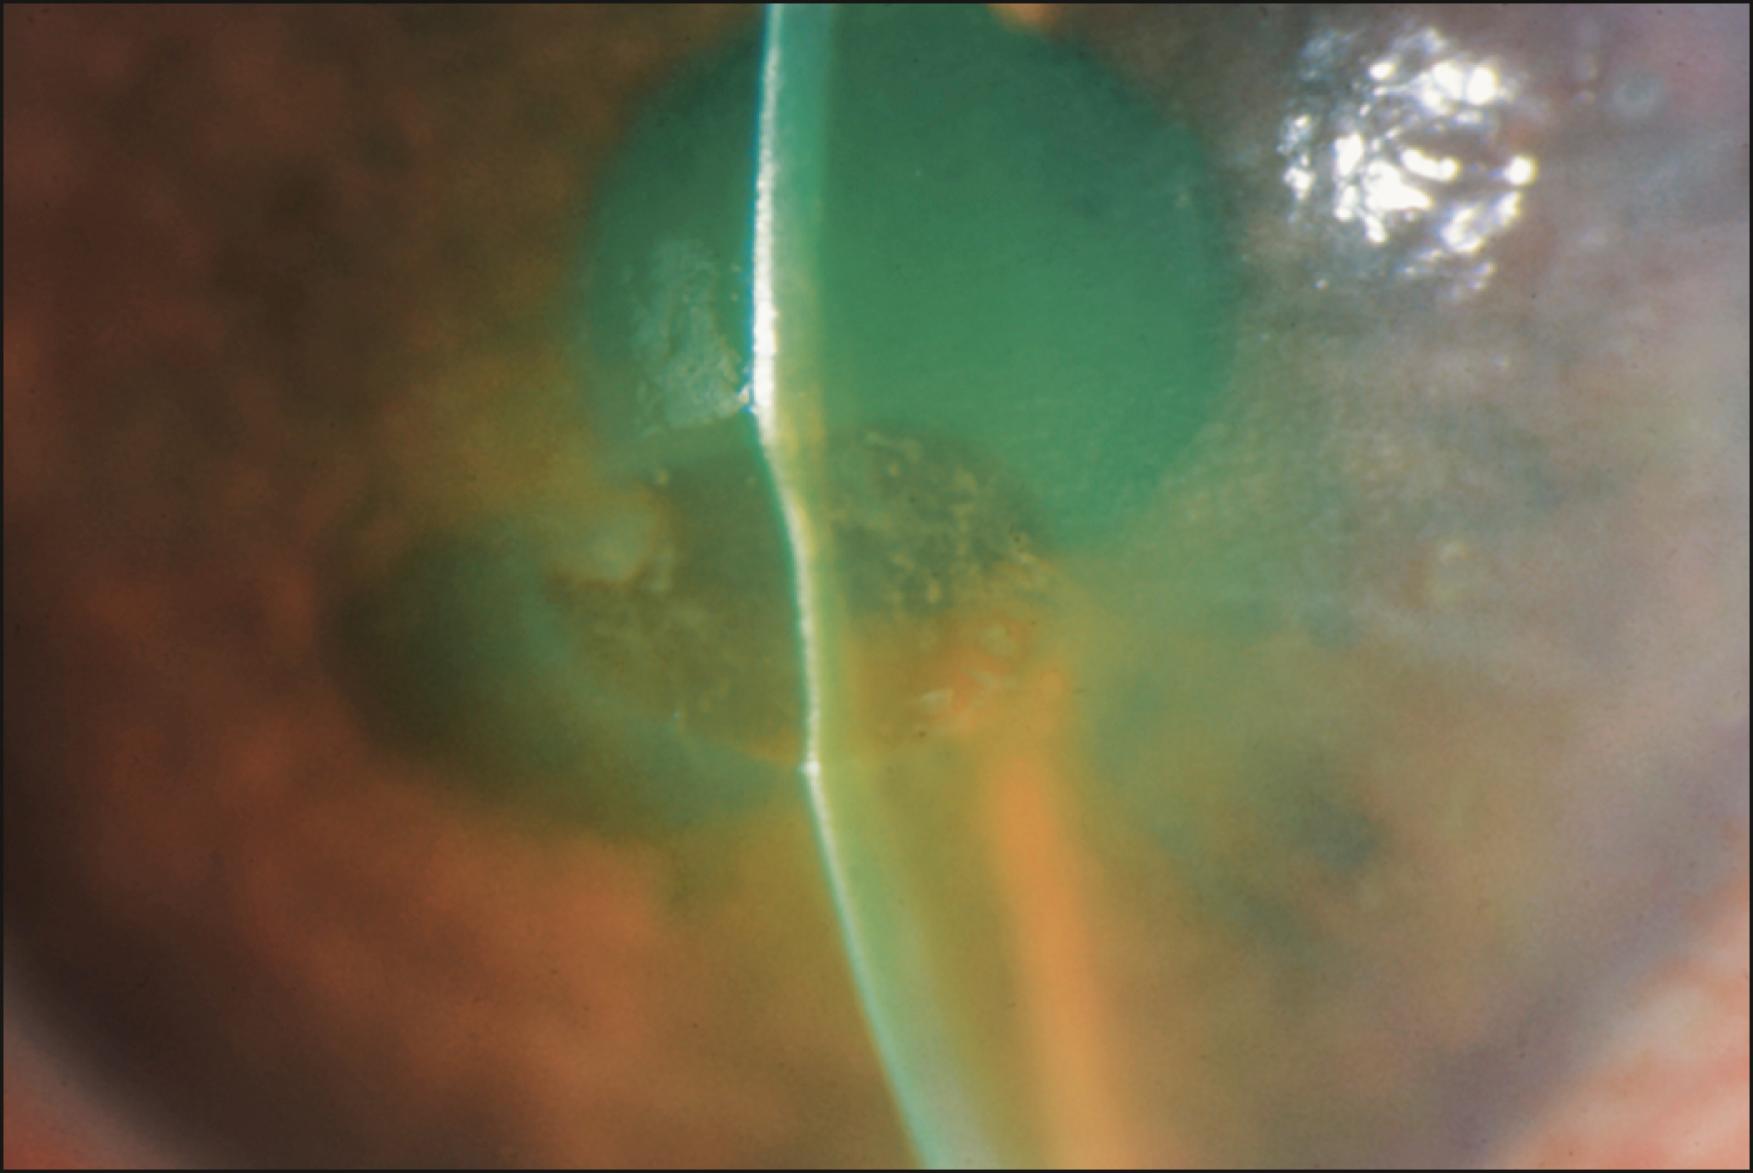

Fluoroquinolones are widely prescribed for anterior segment infections. Both in vitro and in vivo evidence largely demonstrates good ocular surface tolerance. , Delayed hypersensitivity may produce mild punctate epitheliopathy, conjunctival hyperemia, and local irritation. Some animal studies suggest delayed corneal wound healing with second-, third-, and fourth-generation fluoroquinolones, particularly at higher concentrations, with potential keratocyte death. The placement of Besivance (besifloxacin) on the stromal bed under a bandage contact lens in the setting of an epithelial defect may delay reepithelization, possibly secondary to the drug’s carbomer-containing polymer vehicle. Increased ulcer perforation with fluoroquinolone therapy has been reported in several clinical studies of microbial keratitis, but not others. , White corneal micro and macroprecipitates of ciprofloxacin form clinically in 16% of patients and microscopically in nearly 100%, and may be more common in elderly patients due to higher levels of dry eye and a more alkaline ocular surface ( Figs. 68.1 and 68.2 ). , Similar stromal and subepithelial deposits have been reported with other fluoroquinolones in the setting of compromised epithelium, including ofloxacin and gatifloxacin, with variable resolution and effect on visual acuity. Crystallization in human tear film is more likely in formulations with an increased acidic solubility; the pH of ciprofloxacin is 4.5, gatifloxacin 5.5, and ofloxacin 6.4.

Fig. 68.1, Patient with a history of presumed fungal keratitis using hourly ciprofloxacin drops.

Fig. 68.2, Ciprofloxacin deposits. Topical ciprofloxacin will precipitate at physiologic pH. Chalky white deposits accumulate in areas of absent epithelium.